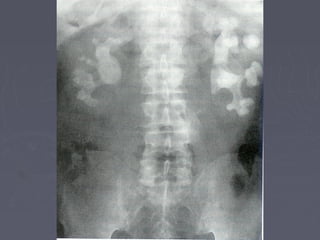

Mis imágenes2005-04 (abr)litiais.jpg